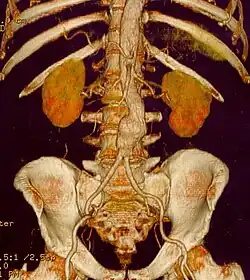

The diagnosis of an abdominal aortic aneurysm can be confirmed by the use of ultrasound. Rupture may be indicated by the presence of free fluid in the abdomen. A contrast-enhanced abdominal CT scan is the best test to diagnose an AAA and guide treatment options.[10]